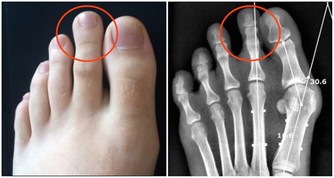

憋尿是一個壞習慣,長期下來容易導致尿路感染、前列腺炎,還很傷腎。

另外,憋尿還會誘發膀胱癌。研究發現,有憋尿習慣者,患膀胱癌風險比一般人高3~5倍。

所以,大家還是要養成按時排尿的習慣,否則傷害日積月累,到那時後悔就來不及了!